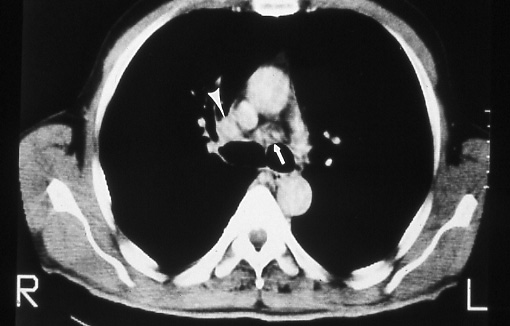

Fig. 45b: Computed tomographic scan of the chest shows a portion of the right upper lobe tumor just lateral to the superior vena cava (arrowhead). A 1.5-2.0 cm. lymph node (arrow) is seen anterior to the carina, T3 N2 M0, stage IIIA disease.